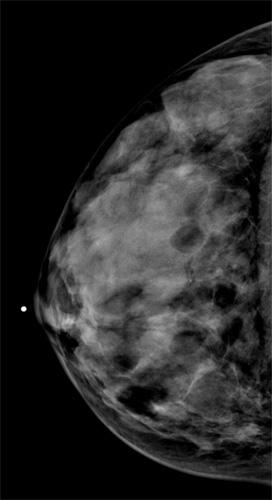

For her study, Arleo and a team of researchers analyzed data on screening mammography at New York – Presbyterian Hospital — Weill Cornell Medical College between 2007 and 2010. Over the four years, 43,351 screening exams were performed, which led to the detection of 205 breast cancers.

Of the women screened in the study, 14,528, or 33.5 percent, were between the ages of 40 and 49. Of the 205 breast cancers detected, 39 (19 percent) were found in the 40-49 age group. Of those cancers, more than 50 percent (21 of 39) were invasive. Only three of the women between the ages of 40 and 49 diagnosed with cancer had a first-degree relative with pre-menopausal cancer.